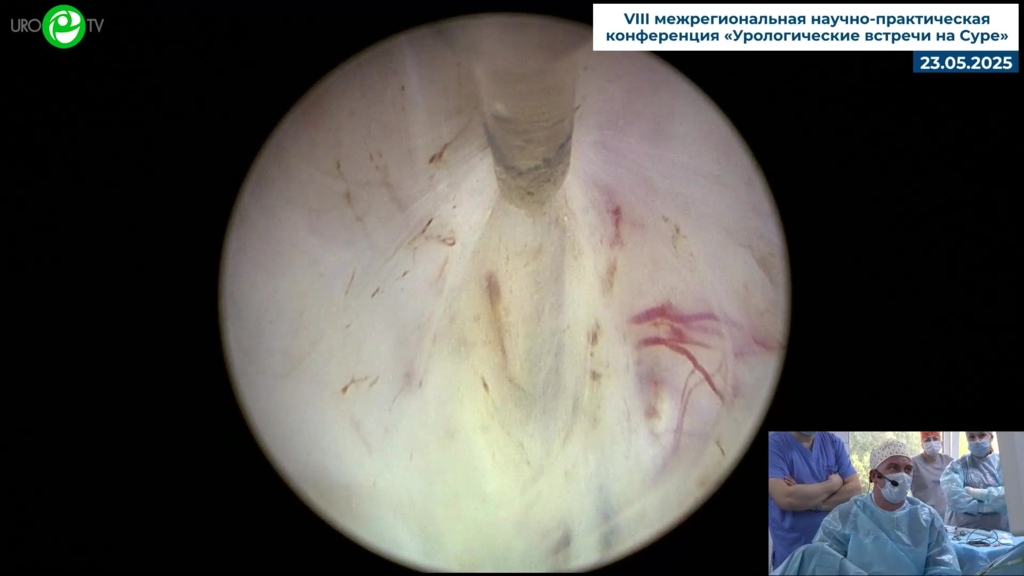

Гоняев А.Р. - Лазерная гольмиевая энуклеация предстательной железы (лазер MuitiPulse Ho)

03 июн 2025

ДГПЖ